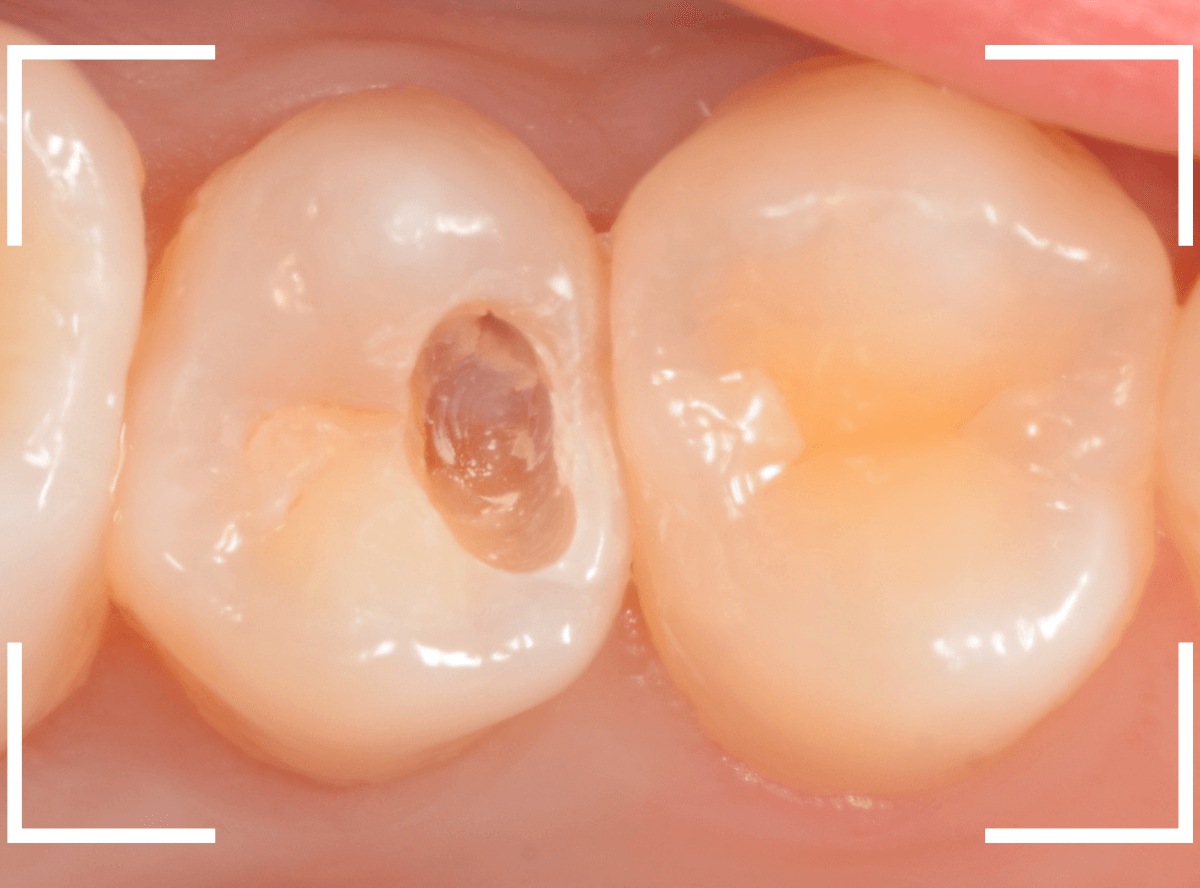

Case.13 虫歯治療とジルコニア・インレー

つめものが外れてしまったという訴えで来院された患者さんです。

外れてしまった歯の中が虫歯になっていますね。

慎重に虫歯を除去したところです。

幸い、虫歯は深くなくほっとしました。

もともとは銀歯が入っていたそうですが、今後は金属を使わない治療を受けたい、という事でジルコニア・インレーで治療する事になりました。

虫歯を削った部分をお薬をつめて、形を整えます。